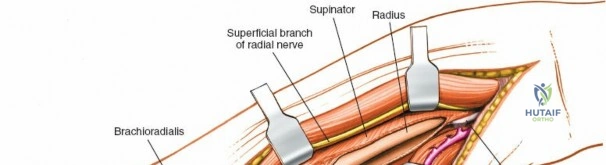

Deep Surgical Dissection: Exposing the Proximal Third

Exposing the proximal third of the radius requires extreme vigilance due to the proximity of the posterior interosseous nerve. The key anatomical landmark here is the insertion of the biceps tendon. Follow the biceps tendon distally to its insertion on the bicipital tuberosity of the radius. A small bursa lies just lateral to the tendon; incise this bursa to gain initial access to the proximal radial shaft. Because the radial artery lies superficial and medial to the tendon at this level, all deep dissection must remain strictly lateral to the biceps tendon.

The proximal radius is draped by the supinator muscle. The PIN passes directly through the belly of the supinator. To protect the nerve, the forearm must be fully supinated. Supination dynamically rotates the radius, carrying the insertion of the supinator anteriorly and simultaneously displacing the PIN laterally and posteriorly, safely away from the surgical field.

With the forearm fully supinated, identify the broad insertion of the supinator on the anterior aspect of the radius. Incise the supinator directly along the line of its insertion onto the bone. It is critical to detach the muscle by dividing its insertion sharply at the bone, rather than splitting the muscle belly, which would risk cutting the PIN.

Proceed with strict subperiosteal dissection, elevating the supinator laterally off the bone. This is one of the rare instances in orthopedic surgery where the safety gained by staying in a subperiosteal plane completely outweighs the theoretical vascular damage to the bone caused by periosteal stripping. The elevated supinator muscle belly now acts as a protective cushion for the PIN.

Retractor Placement and Fixation Technique

Once the proximal radius is exposed, great care must be taken with retractor placement. Never place Hohmann or levering retractors blindly around the posterior surface of the radial neck. Because the PIN may touch the bone posteriorly in up to 25% of patients, a posteriorly placed retractor can easily crush the nerve against the radial cortex. Instead, use gentle right-angle retractors or place retractors only on the anterior and lateral aspects of the bone, utilizing the elevated supinator as a shield.